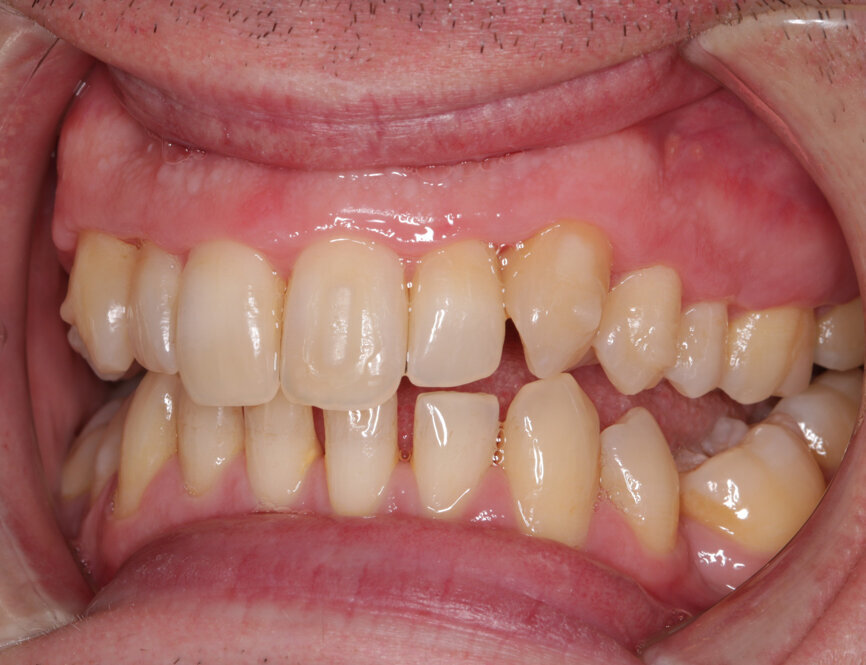

A 32-year-old male patient presented to our practice after he saw that we provide GDP orthodontics on our website. He came from an NHS practice and it was agreed that he would remain with that practice for his routine care. He was fit and well, took no medication, had no allergies and was a non-smoker. However, he was struggling with his oral hygiene and did not like the appearance of his maxillary teeth, specifically the colour and the alignment. He was not keen on the idea of fixed orthodontic appliances, but had heard about clear aligners.

My examination revealed nothing abnormal with his extra- or intra-oral soft tissue, temporomandibular joint or range of motion. However, his oral hygiene was poor, which was not helped by the crowding of his maxillary anterior segment. In addition, tooth #48 was carious. I carried out a full orthodontic assessment (Table 1) and took photographs.

I explained that the maxillary teeth could and should be aligned, as this would likely result in easier cleaning of the teeth, plus it would improve the appearance. The patient and I agreed that the mandibular teeth could remain untouched, as this would keep the cost down, but mainly because they did not bother him. The priority was to stabilise his periodontal condition. A basic periodontal examination Code 3 and heavy bleeding were recorded in each sextant. At that visit, I performed a gross scaling using the ultrasonic scaler and used a model to demonstrate both the use of flossettes and an oscillating toothbrush.

Looking back at this case, it is apparent that I had not quite mastered my photography, leading to darker before photographs. I steadily eliminated errors in my technique throughout the case by use of better mirrors, de-steaming, better retraction, greater knowledge of exposure and suchlike. This case just happened to be right at the start of the learning curve. I also wish I had taken more photographs during treatment.

Fig. 2: Pre treatment smile